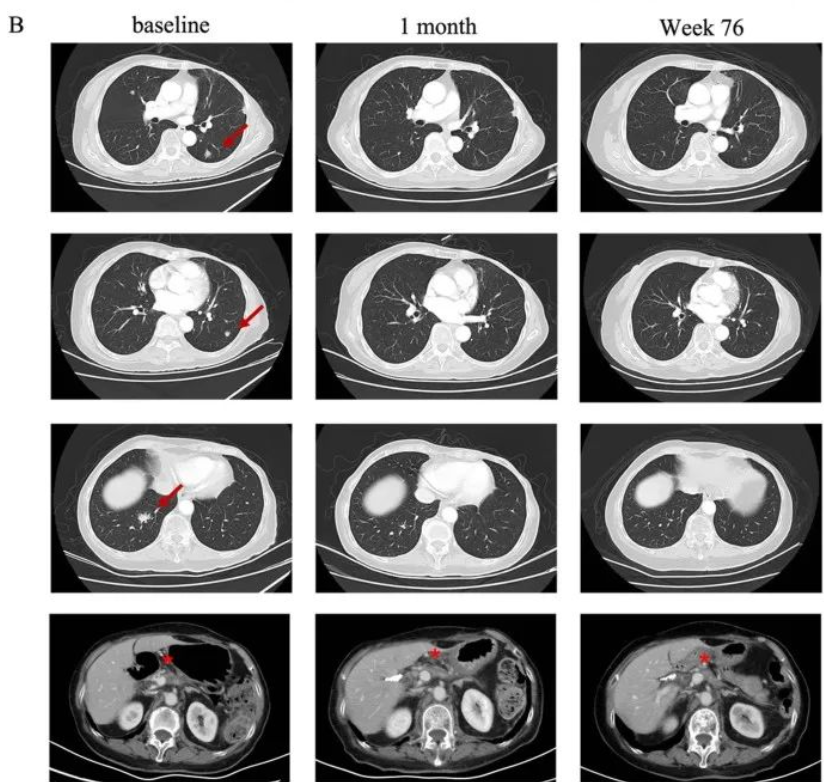

典型病例2

一名75岁的高龄女性胰腺癌患者,于2019年5月接受了手术切除,诊断为pT2N0期胰腺癌。术后随访5个月时发现肺转移。自2019年12月开始一线S-1单药化疗,在行手术野姑息性放疗期间肺部转移。经检测其Claudin18.2表达为3+/60%后入组CT041临床试验。

在进行氟达拉滨、环磷酰胺、白蛋白紫杉醇方案清淋预处理后,患者于2021年7月输注CT041细胞输注。输注后患者出现2级CRS,经托珠单抗治疗后恢复。患者在CT041输注后第4周进行首次肿评即达到部分缓解(PR),后肺部靶病灶进一步消失达到完全缓解。截至2023年7月末次随访时患者仍处于持续缓解状态。